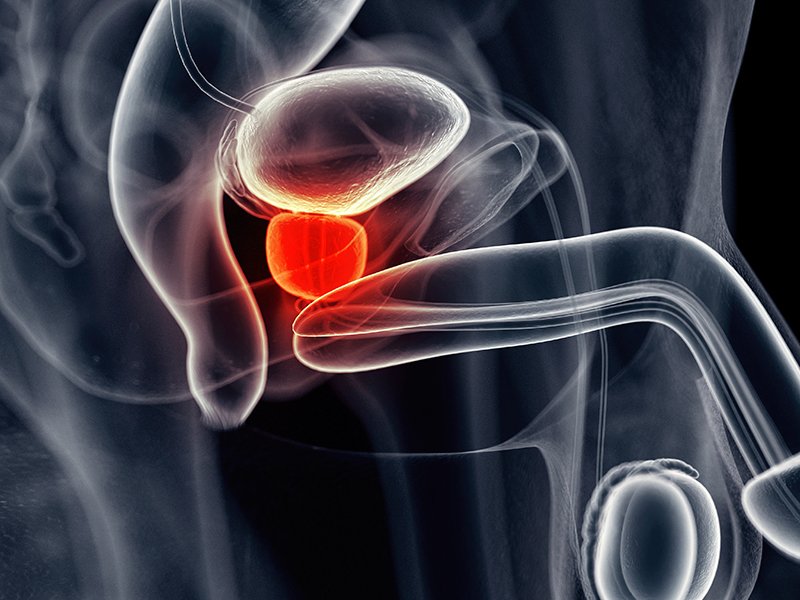

Бессимптомный простатит в медицине зачастую классифицируют как асимптоматическое хроническое заболевание. По своему типу проблема представляет собой поражение предстательной железы, которое носит воспалительный характер. Данный тип заболевания протекает без явных болевых симптомов, из-за чего оно очень часто довольно поздно диагностируется. Практика показывает, что из-за этого же далеко не все мужчины знают о том, что в их организме присутствует описываемая проблема.

Весь процесс обследования состоит из целого комплекса процедур. В их число входит проведение общего анализа мочи, УЗИ предстательной железы, а также органов малого таза. Параллельно со всем этим пациент подвергается пальцевому исследованию простаты, что осуществляется через прямую кишку.